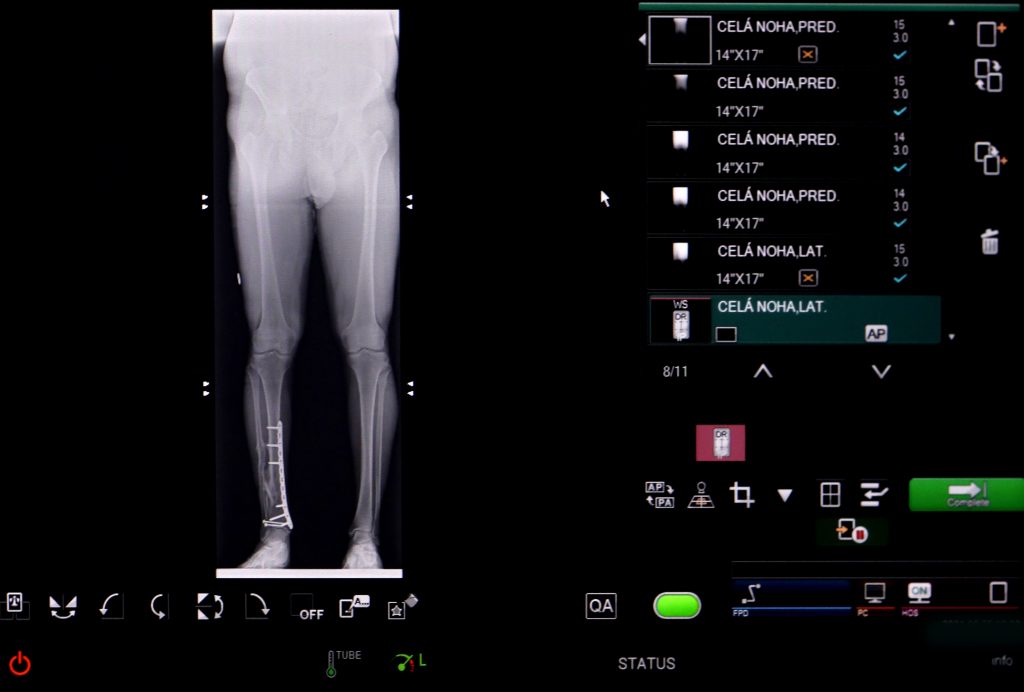

Univerzitná nemocnica L. Pasteura Košice získala prvý a jediný ortopedický digitálny panel na Slovensku, ktorý zaručí pacientom najkvalitnejšiu rádiodiagnostiku. Umožní to tzv. dlhý detektor (moderný typ FLAT panelu) ako prídavné zariadenie k digitálnemu röntgenovému prístroju.

Vďaka inovatívnemu FLAT panelu dokáže digitálny RTG prístroj snímkovať pacienta v stoji s rozsahom 124 cm. „Kým bežný röntgen dokáže zobraziť napr. celú chrbticu na viacerých snímkach, tento typ FLAT panelu, alebo ak chcete dlhý detektor, ju dokáže zachytiť jediným záberom na jednej celistvej snímke,“ vysvetľuje MUDr. Henrieta Blašková, primárka Oddelenia rádiodiagnostiky a zobrazovacích metód. „Tento detektor eliminuje riziko opakovania snímkovania z dôvodu prirodzeného pohybu pacienta, čím zároveň zvyšuje presnosť celého vyšetrenia.“

RTG flat panel snimka

Dôležitá diagnostická pomôcka najmä pre ortopédov, úrazových chirurgov a rádiológov

Tzv. dlhý detektor má veľký prínos v diagnostike pacientov po úraze, či v diagnostike detí s vývojovými chybami chrbtice, dolných aj horných končatín, ako aj pri získaných ortopedických poruchách napr. skolióza, kyfóza. „Vďaka celistvej RTG snímke dlhšej časti tela, dokážeme veľmi detailne a presne rozlíšiť poúrazové deformity, vrátane skrátenia končatín napr. po zlomeninách. Takáto analýza umožňuje presnejšie plánovanie rekonštrukčných operačných výkonov v uvedenej skupine pacientov,“ konkretizoval úrazový chirurg MUDr. Peter Cibur, PhD. z Kliniky úrazovej chirurgie (KÚCH).